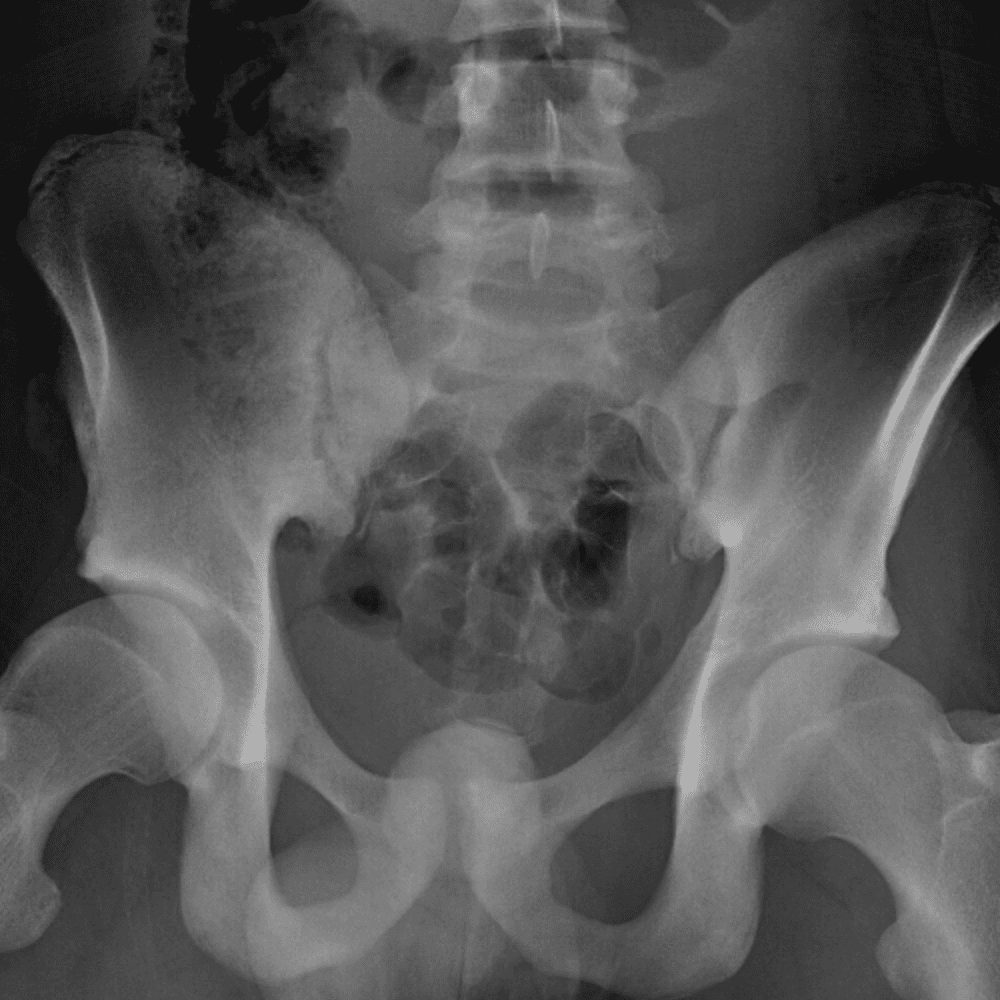

通过包含微妙或困难的病例和一些正常病例来模拟值班。

30 病例